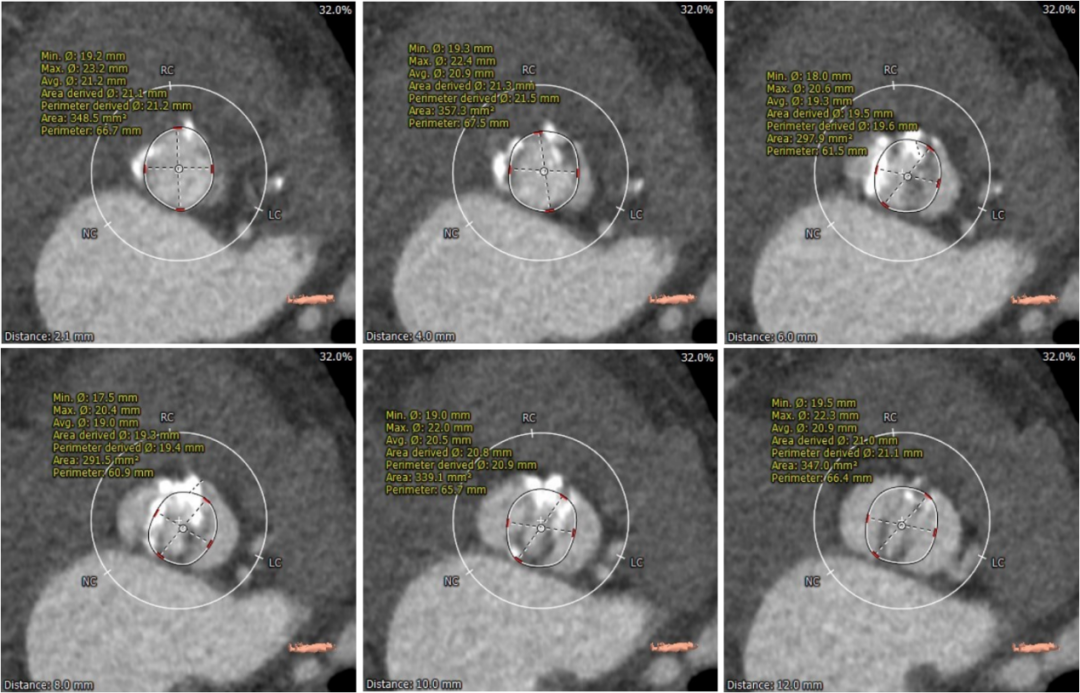

术前CT评估

Type0型二叶式主动脉瓣,重度钙化,钙化发布不均,位置靠右前侧,根据钙化形态预估,术中钙化推移难度较大,对人工瓣膜形态影响较大,存在人工瓣膜移位及瓣周漏风险。

左冠高度稍低,左冠起始处可见局限钙化,左冠瓣瓣叶长度偏长,综合瓦氏窦内径等因素考虑,左冠存在遮挡风险。

左室腔内径有增大,心室壁增厚。

入路血管多处钙化,腹主动脉分叉前病变较重,双侧血管内径良好,整体入路血管条件尚可。

主动脉根部测量

瓣上结构测量

冠脉阻挡风险及钙化评估

外周血管入路评估